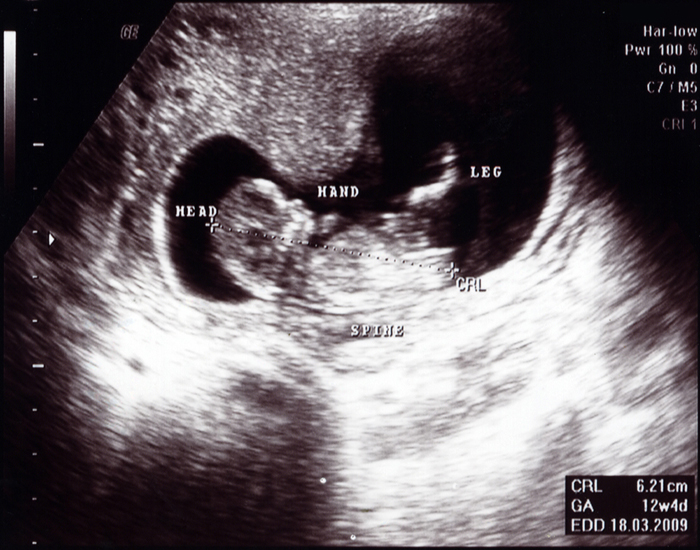

12 Haftalık Gebelik Ultrason Görüntüleri

12 haftalık bebeğin boyu kaç cm olmalıdır? 12 haftalık bebek kalp atışı kaç olmalı? Haftada da bebeğinizin hareketlerini hissedemezsiniz.

12 Haftalık Gebelik Ultrason Görüntüleri

En Detaylı Ultrason Terimleri Rehberi

12 haftalık gebelikte bebeğin boyu ve kilosu. Ancak kasları geliştikçe yavaş yavaş beyin sinyallerine cevap vermeye başlayacak. 12 haftalık bebeğin görüntüsü hamileliğin 12.